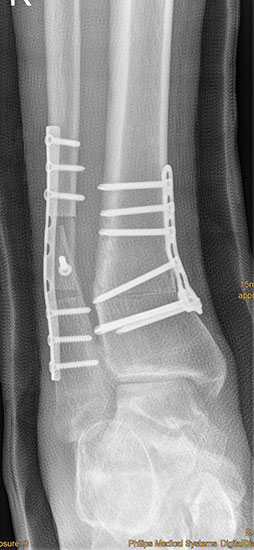

Auch hier wird die Korrektur im CORA (Center oft Rotation and Angulation) durchgeführt. Primär werden intraoperativ unter Bildwandler Kontrolle Kirschner Drähte als Sägelehre konvergierend eingebracht. Dann wird der geplante medialbasige Keil mit der oszillierenden Säge entfernt. Die laterale Kortikalis sollte geschont werden, sie dient als Drehpunkt für die Osteotomie. Die Osteosynthese kann dann im Sinne einer Zuggurtung ein besonders stabiles Konstrukt bilden. Liegen mehrdimensionale Deformitäten vor, die eine Korrektur in Translations- und Rotationsebene erfordern, ist eine Durchtrennung der lateralen Kortikalis notwendig, ebenso bei ausgedehnten Korrekturen mit Keilhöhen über 10mm 218.

Wir benutzen zur Osteosynthese 3,5 mm LCP T-Platten. In der intraoperativen Röntgenkontrolle kann im seitlichen Bild die Zentrierung des Talus überprüft werden, und ggf. durch eine milde extendierende oder flektierende Korrekturkomponente verbessert werden 18. Eine begleitende Deformität der Fibula korrigieren wir üblicherweise mit einer z-förmigen Osteotomie die wir mit einem 1/3 Rohrplättchen sowie einer Zugschraube sichern 18.